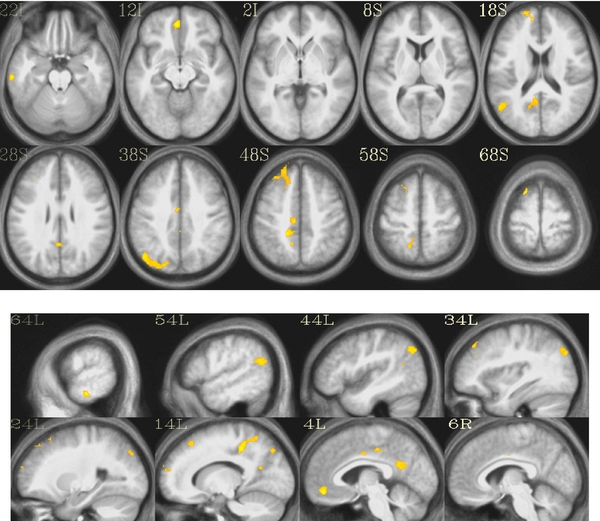

Giuseppe Pagnoni, PhD, Emory assistant professor of psychiatry and behavioral sciences, and co-workers used functional magnetic resonance imaging (fMRI) to examine changes in blood flow in the brain when people meditating were interrupted by stimuli designed to mimic the appearance of spontaneous thoughts.

The authors found that differences in brain activity between experienced meditators and novices after interruption could be seen in a set of areas often referred to as the "default mode network." Previous studies have linked the default mode network with the occurrence of spontaneous thoughts and mind-wandering during wakeful rest.

After interruption, experienced meditators were able to bring activity in most regions of the default network back to baseline faster than non-meditators. This effect was especially prominent in the angular gyrus, a region important for processing language.